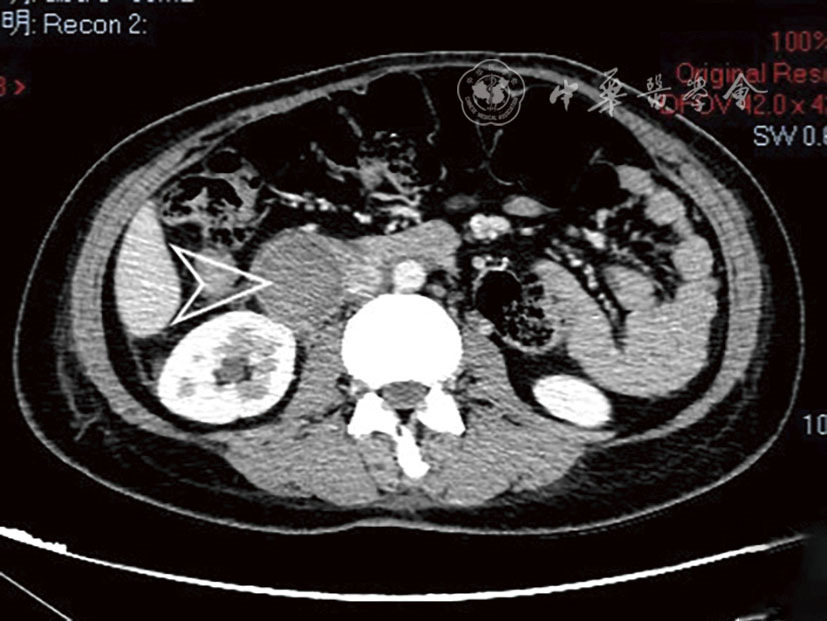

Tao Chen, Hongjian Shi, Liang Zhou, Zhen Gan.

Interventional treatment for delayed postoperative hemorrhage after gastric and pancreatic-biliary surgery

[J]. Chinese Journal of Interventional Radiology(Electronic Edition), 2024, 12(01): 39-44.